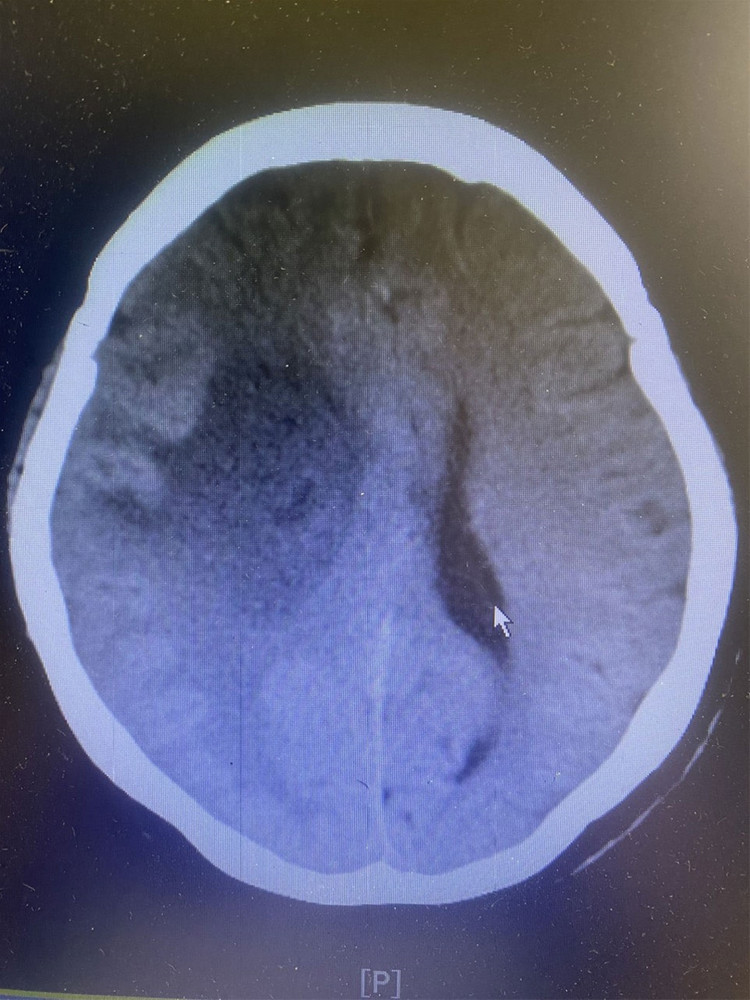

Người bệnh là D. T. C. 66 tuổi (trú tại Trưng Vương – Uông Bí), người bệnh có tiền sử tăng huyết áp. Khoảng 3 ngày trước khi nhập viện, người bệnh có biểu hiện yếu nửa người trái. Trên hình ảnh chụp cắt lớp vi tính sọ não phát hiện khối u não vùng đỉnh phải kích thước 4,7x5,6cm.

| Khối u não khổng lồ trên phim chụp |